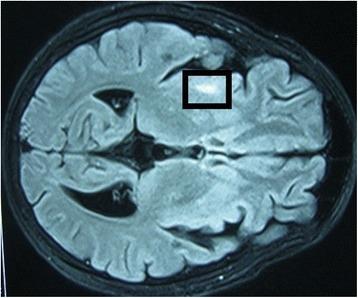

A 17-year-old adolescent boy of Sri Lankan Moor heritage was taking long-term immunosuppressants for nephrotic syndrome. He presented to hospital with focal fits affecting his left arm. He later developed choreiform movements of the same arm, progressing to epilepsia partialis continua and weakness. The gradually evolving focal neurological signs and underlying immunosuppression raised the possibility of localized cerebral infection or inflammation. Analysis of his cerebrospinal fluid showed lymphocytosis with normal cellular morphology. Magnetic resonance imaging was suggestive of progressive vasculitic infarctions of the cerebral cortex and basal ganglia. There was no evidence of active autoimmune or viral disease on hematological investigations, but molecular amplification detected Mycobacterium tuberculosis in his cerebrospinal fluid. Although our patient had been established on isoniazid preventive treatment for eight months before the episode, tuberculosis was nonetheless considered to be the most likely cause of the cerebral vasculitis. He was treated with a trial of anti-tuberculosis treatment, including streptomycin and adjunctive steroids, and made an uneventful recovery.

一名17岁具有斯里兰卡摩尔族血统的青少年男性因肾病综合征长期服用免疫抑制剂。他因左臂局灶性抽搐入院。随后该手臂出现舞蹈样动作,进而发展为持续性部分性癫痫发作和无力。逐渐演变的局灶性神经体征及潜在的免疫抑制提示存在局限性脑感染或炎症。其脑脊液分析显示淋巴细胞增多,细胞形态正常。磁共振成像提示大脑皮质和基底节区进行性血管炎性梗死。血液学检查未发现活动性自身免疫性或病毒性疾病证据,但分子扩增检测在其脑脊液中发现结核分枝杆菌。尽管我们的患者在此次发作前已接受异烟肼预防性治疗8个月,但结核病仍被认为是脑血管炎最可能的病因。他接受了包括链霉素和辅助性类固醇在内的抗结核治疗试验,恢复过程顺利。